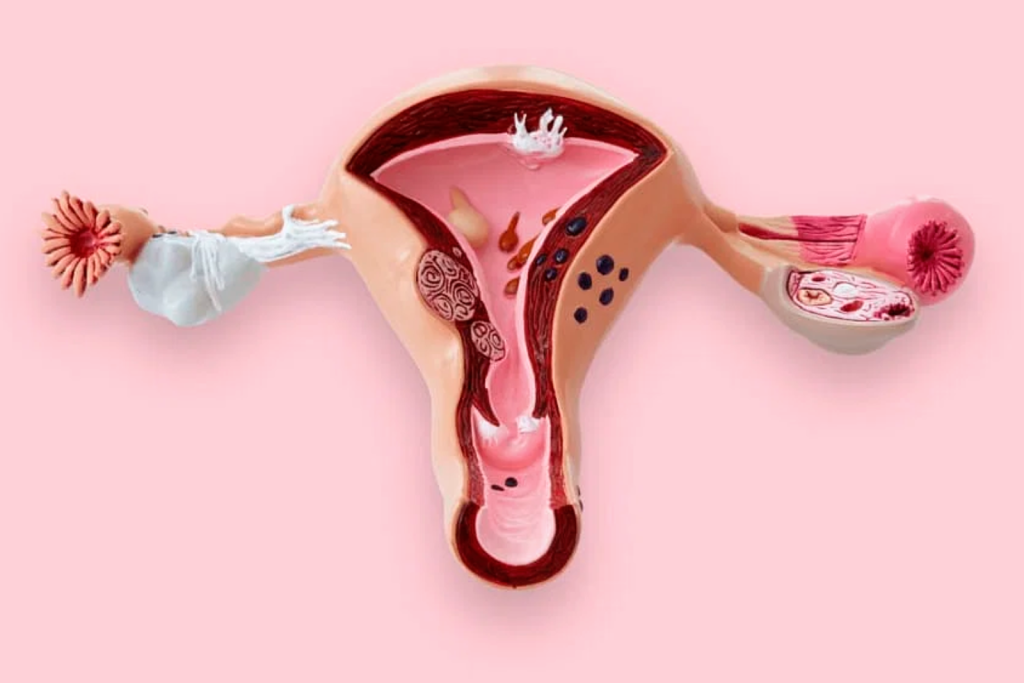

Polycystic Ovarian Syndrome

Hypogonadism